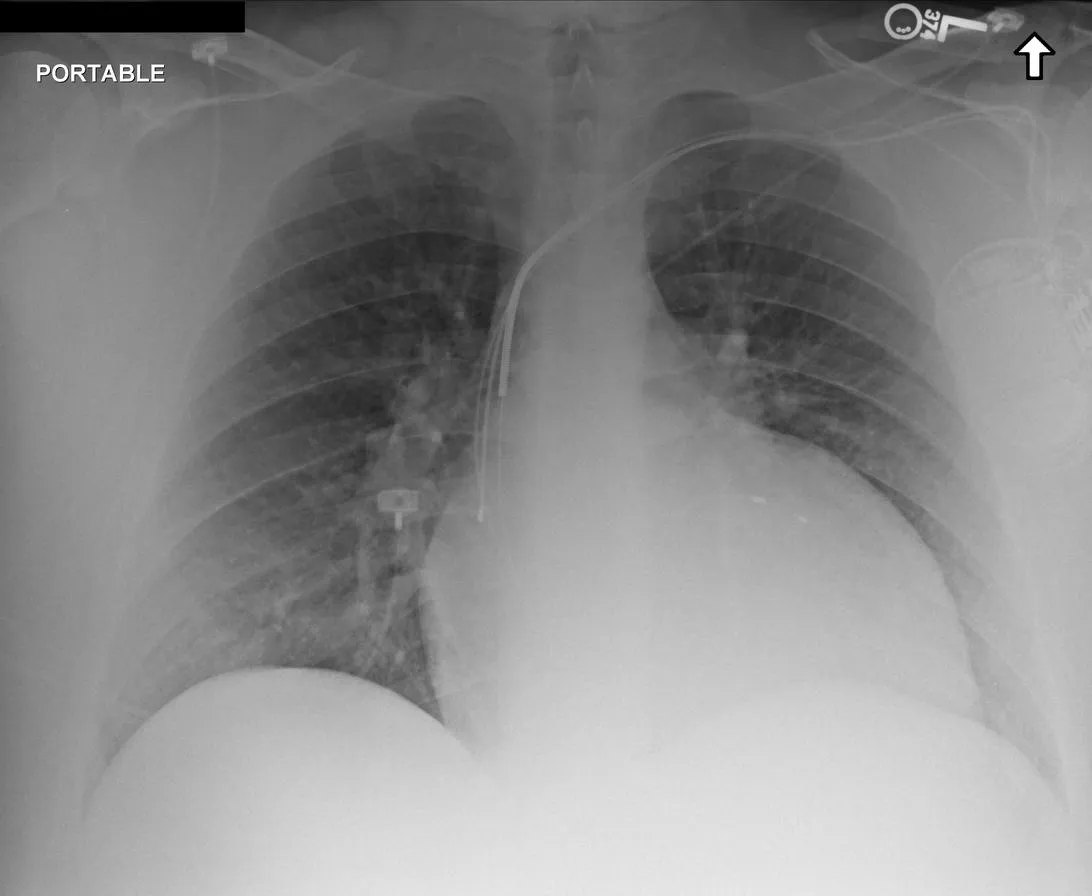

Public Dataset Integration for Breadth. We leverage established open-source datasets (e.g., MIMIC-CXR [28], CheXpert [24], and ROCO [47]) to provide a foundational layer of visual variety. These datasets offer a vast quantity of samples covering common pathologies and standard anatomical views. However, raw annotations in public datasets are often noisy or limited to binary classification tags (e.g., “Pneumonia: Positive”).

Stage 3: Multi-Granularity Instruction Formatting. To enable the model to handle various user intents, we do not simply pair the image with a single caption. Instead, we generate diverse instruction-response pairs derived from the generated caption. These include: (1) Descriptive Instructions (e.g. “Describe the findings in this chest X-ray.”), (2) Diagnostic Q&A (e.g. “Is there evidence of pleural effusion? If so, describe its location.”), (3) Localization Tasks (e.g. “Identify the region responsible for the patient’s shortness of breath.”), and (4) Reasoning Prompts (e.g. “Based on the visual evidence, what is the most likely diagnosis and what follow-up is recommended?”).

The training dataset is built mainly from radiology imaging data (e.g., X-rays, CT scans, MRI) and public de-identified radiology datasets, which include pathological/normal cases, metadata and expert annotations. Given the varying diagnostic complexity and tool utility of raw radiology data, a two-stage filtering pipeline is adopted to create an effective RL training set:

Medical report generation stresses long-form coherence and, more importantly, faithfulness: the ability to describe findings without introducing subtle hallucinations or unsupported claims. Evaluation in this category is particularly sensitive to protocol choices (e.g., what constitutes an omission versus an incorrect addition), which motivates our unified prompting, structured output requirements where applicable, and complementary inhouse faithfulness tests. Tab. 7 lists the report benchmarks included.